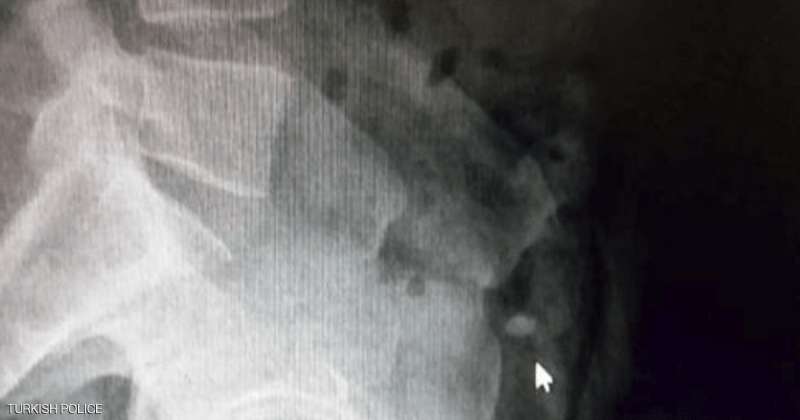

وأمرت الشرطة بنقل السارق إلى المستشفى، من أجل إجراء عملية جراحية للعثور على الخاتم، ما لم يعد الأيرلندي الخاتم بـ"الطريقة الطبيعية".

وتابعت وسائل إعلام تركية "رحلة" الخاتم، لحظة بلحظة لمدة يومين كان خلالها اللص ينتظر في المستشفى بعدما تناول أدوية تسهّل الإخراج، وذلك تحت حراسة الشرطة.

وقد قفز مرارا في المستشفى لتحريك الخاتم في أحشائه لمدة 36 ساعة، لكن جهوده كانت بلا جدوى، وبعد ذلك لجأت السلطات إلى استخراج الألماس عبر عملية جراحية.